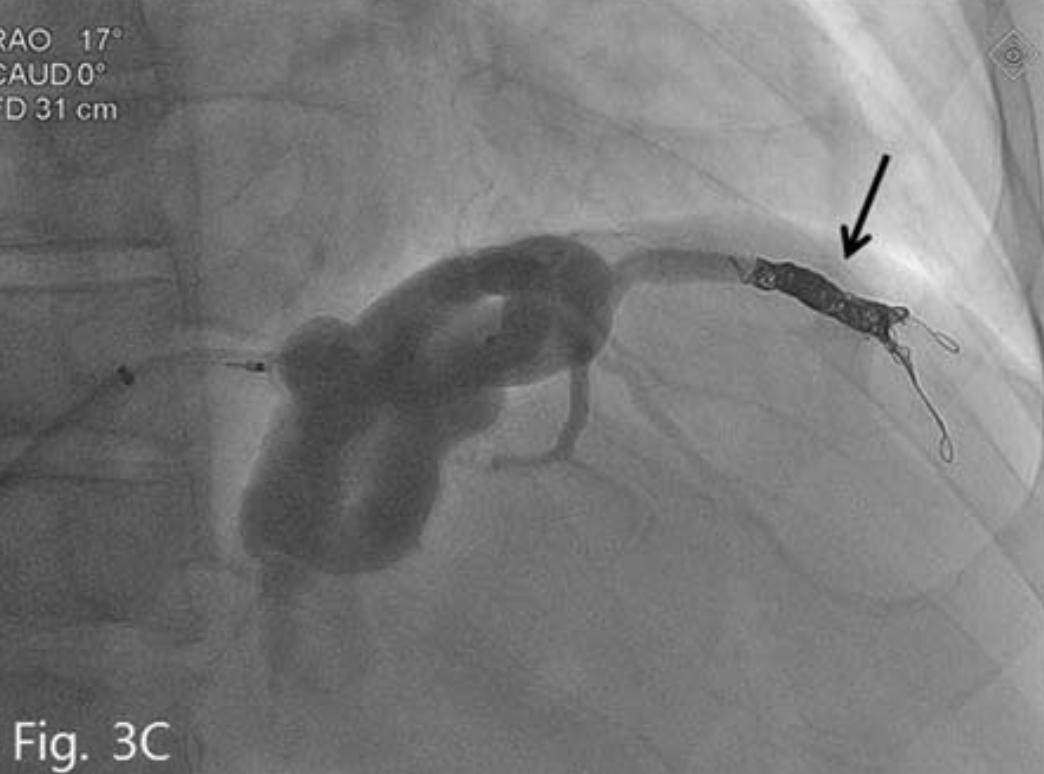

복부 전산화 단층촬영(CT)에서 간경화 및 비장비대의 소견과 함께 위식도 정맥류가 관찰되었다. 위정맥류의 경우 위신 단락 (gastrorenal shunt)은 보이지 않았으며, 대신 현저하게 늘어나 있는 위하대정맥 단락 (gastrocaval shunt)이 확인되었고 이것이 위정맥류의 주 유출정맥으로 생각되었다(Fig. 2A-C).

Fig. 2

Contrast enhanced CT (A~C) shows esophageal and gastric varices (arrowhead) and gastrocaval shunt (arrow).